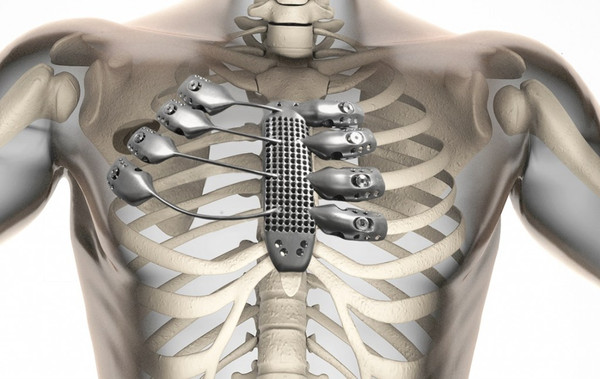

这位病人患有胸壁肉瘤,必须要切除胸骨和一部分的肋骨,然后再以钛金属植入物代替。比起传统方法,3D打印的植入物可以实现完全的定制化,制造速度也更快,而且可以解决现有设计中存在的一些问题。

据了解,此次的手术是由西班牙萨拉曼卡大学医院的团队完成的,所使用的钛金属3D打印植入物则是由澳大利亚的医疗设备公司Anatomics制造的。该公司首先利用从病人身上获取的扫描数据创建了植入物的3D数字模型,然后利用使用澳洲联邦科学与工业研究组织(CSIRO)在今年5月刚刚建立的Lab 22中的Arcam 3D打印机制作出了最终的成品。该设备使用的是电子束熔融技术,能够融化钛金属粉末,然后以层层叠加的方式制造金属物体。